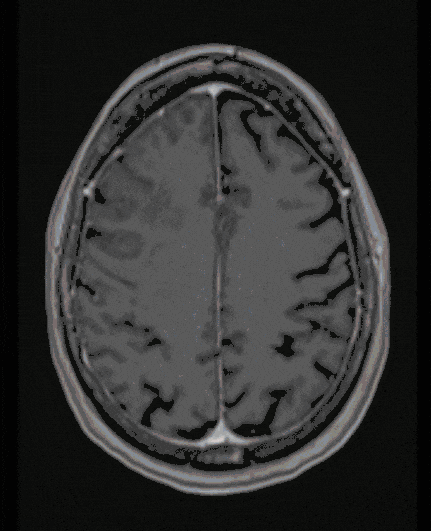

Meningioma

Meningiomas are mostly benign tumors that can grow to considerable sizes due to their character and slow growth. They threaten the function of the brain and its exiting nerves (cranial nerves of the brain stem).